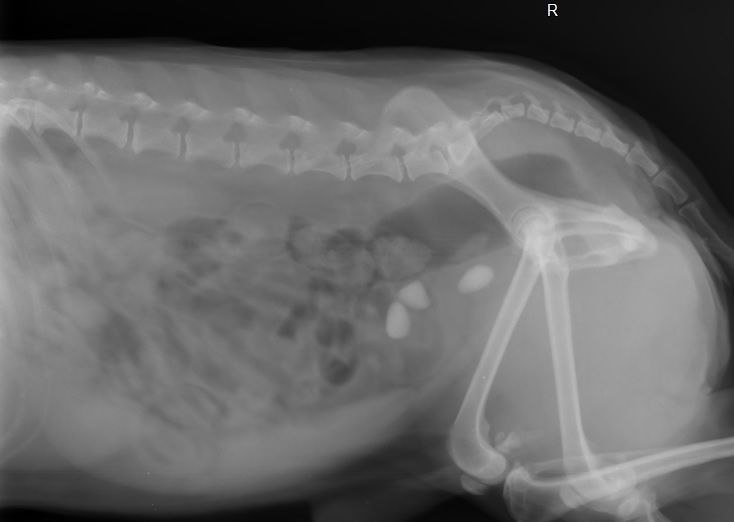

- Завороте кишок или непроходимости — особенно у собак крупных пород;

- Съемка: делается 1–3 снимка с разных ракурсов.

- Расшифровка: врач-рентгенолог анализирует снимки и готовит заключение.

Можно ли делать рентген беременной кошке?

Только по жизненным показаниям. Избегайте облучения в первом триместре. При необходимости мы используем защиту и минимальную дозу.